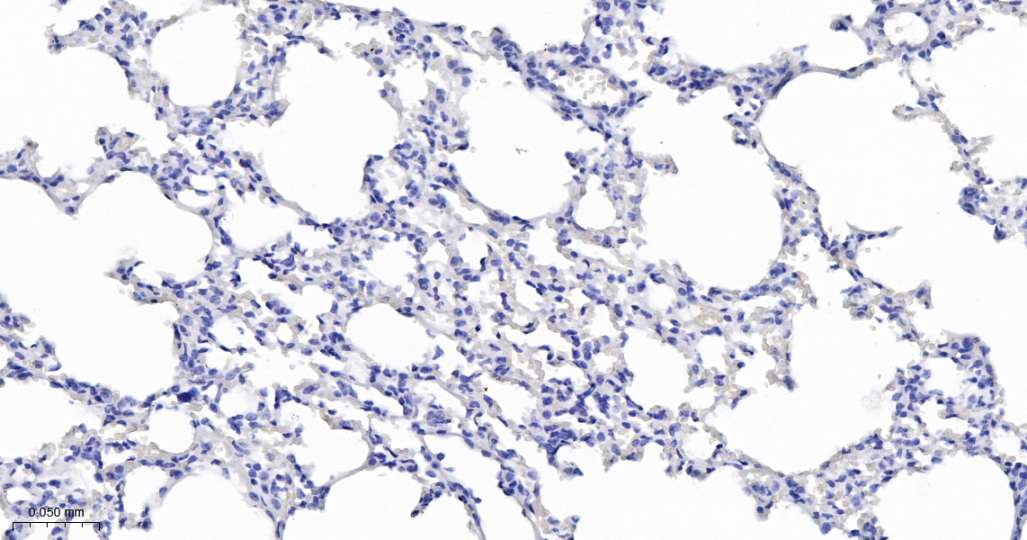

Immunohistochemical analysis of paraffin embedded Mouse lung tissue slide using IHC0630M (Mouse MOG IHC Kit).